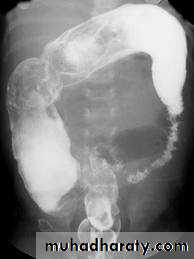

A barium follow-through procedure is a type of medical imaging technique. It is used to evaluate the presence of disease in a person's small intestine.Examination

Barium follow through x-rayThe patient drinks a contrast medium containing barium sulfate. This contrast medium appears white on x-rays, and shows the outline of the internal lining of the bowel. X-ray images are taken as the contrast moves through the intestine, commonly at 0 minutes, 20 minutes, 40 minutes and 90 minutes. This enables the radiologist to assess the bowel as it becomes visible. The test is completed when the Barium is visualised in the terminal ileum and Caecum, which marks the beginning of the large bowel. This is one of the most common places for pathology of the bowel to be found, therefore imaging of this structure is crucial. The test length varies from patient to patient as bowel motility is highly variable.

Radiological appearance of Mal absorption syndrome

* Loss of normal feathery appearance of the small bowel

* Flocculation & segmentation of the Ba

* Widening of the spaces between bowel loops due to mucosal edema

*+/_ spiky appearance of the small bowel loops